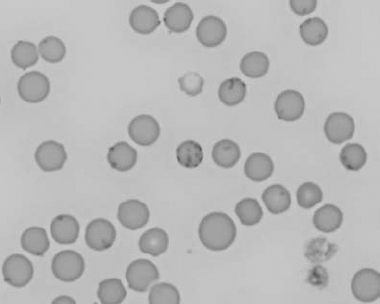

Figure 1.3 Canine blood film showing acanthocytes (also see color section).

Figure 1.4 Canine blood film showing anisocytosis (also see color section).

Figure 1.5 Bovine blood film showing basophilic stippling within a macrocyte as part of the regenerative response (also see color section).

Figure 1.6 Canine blood film showing basophilic stippling due to lead toxicosis (also see color section).

Figure 1.7 Canine blood film showing blister cells due to oxidative damage (also see color section).

Figure 1.8 Canine blood film showing codocytes. Up to 50% codocytes may be normal in a dog (also see color section).

Figure 1.9 Canine blood film showing eccentrocytes due to oxidative damage (also see color section).

Figure 1.10 Canine blood film showing echinocytes I (also see color section).

Figure 1.11 Canine blood film showing echinocytes III (also see color section).

Figure 1.12 Feline blood film showing echinoelliptocytes (also see color section).

Figure 1.13 Canine blood film showing Heinz bodies and ghost cells due to oxidative damage. There are also several polychromatophils (also see color section).

Figure 1.14 Canine blood film stained with new methylene blue, to demonstrate Heinz bodies (also see color section).

Figure 1.15 Canine blood film showing keratocytes and schizocytes (erythrocyte fragments) due to fibrin strand injury. A codocyte and a polychromatophil also appear in the field (also see color section).

Figure 1.16 Feline blood film showing Mycoplasma hemofelis organisms (hemobartonellosis). Organisms are not always visible in blood smears from infected cats (also see color section).

Figure 1.17 Canine blood film showing several macrocytes (also see color section).

Figure 1.18 Canine blood film showing a metarubricyte There is also a polychromatophilic macrocyte in the field (also see color section).

Figure 1.19 Canine blood film showing microcytic, hypochromic erythrocytes consistent with iron deficiency anemia. There are two polychromatophils in the field, indicating that the anemia is regenerative (also see color section).

Figure 1.20 Canine blood film showing two macrocytes with nuclear remnants (also see color section).

Figure 1.21 Bovine (calf) blood film showing marked poikilocytosis (normal?) (also see color section).

Figure 1.22 New methylene-blue-stained Canine blood film showing reticulocytes (also see color section).

Figure 1.23 Canine blood film showing rouleaux formation (also see color section).

Figure 1.24 Canine blood film showing spherocytosis and polychromasia due to immune-mediated hemolytic anemia (also see color section).

Figure 1.25 The red blood cell cytoskeleton.